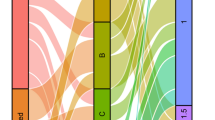

Historically, the role of systemic therapy for brain metastases has been limited due to the poor penetration of most chemotherapeutic drugs across the blood–brain barrier (BBB). Recently, however, there has been growing evidence that immune checkpoint inhibitors (ICI) can achieve durable responses even for brain metastases [25]. Although these agents are unable to cross the BBB, due their large molecular size, it is believed that activated tumor-specific T-cells can do so [26]. There is good evidence from numerous retrospective studies that SRS and ICI interact synergistically; the main mechanism of action responsible for such positive outcomes appears to be activation of the immune-cytokine cascade by high dose ablative radiation [14]. More specifically, extensive tumor cell injury and death produced by high dose radiation induces a massive release of tumor-specific antigens, as well as pro-inflammatory and pro-oxidant cytokines. Radiation also promotes antigen presentation through activation and maturation of dendritic cells, as well as an increase in effector T cell traffic to tumor by increasing major histocompatibility complex, adhesion molecules, costimulatory molecules, heat shock proteins, and death receptors expression [27]. The ultimate downstream effect is a tumor-specific heightened immune response [28, 29]. This benefit can be further magnified through the abscopal effect, in which high-dose radiation causes regression not only of the radiation-targeted tumor, but also of distant sites of cancer that were not targeted by radiation, presumably through a systemic immune-mediated response to the radiation [30]. Here, the effects of high-dose radiation-induced immune response are amplified through immunotherapy, which targets and upregulates antigen processing, and generation and trafficking of effector T cells. The proposed synergistic effects of high-dose radiation and immunotherapy have been demonstrated in several recent retrospective studies [31]. In one such study, Skrepnik et al. performed a retrospective review of melanoma brain metastases treated with SRS and ipilimumab and found that such patients had a very long median survival compared to historical controls. Furthermore, they found that there is an optimal window of time for synergy: patients treated with SRS and Ipilimumab within a 30 days window of time had a superior time to CNS progression, and regional brain control (Fig. 4) [32]. Similarly, a more recent meta-analysis by Lehrer et al. of published studies of melanoma brain metastases treated with SRS and ICI, found that concurrent SRS and immunotherapy had a higher 1-year OS, local control, and regional brain control than non-concurrent therapy [33]. While concurrent SRS and immunotherapy appears to be very effective in controlling the disease, there is a growing concern of radionecrosis (RN) given the synergy. Skrepnik et al. found an overall RN rate of 20.7% but a symptomatic RN rate of only 5% that required treatment with Avastin. Similarly, Lehrer et al. found the rate of any RN to be 0–20.7% across all studies, with a combined rate of 5.3%. Multiple prospective trials are ongoing to determine the efficacy [34], optimal fractionation [35], timing [36], and toxicity [37] of combined stereotactic radiation and immunotherapy.

A Overall survival of melanoma brain metastases patients treated with a combination of SRS and ICI leading to high median survival (median OS = 35.8 months). B Time to progression in the CNS by timing of SRS delivery to administration of ICI; delivery up to 30 days from each other leads to a statistically better time to CNS progression (p = 0.02), suggesting synergism between the 2 modalities